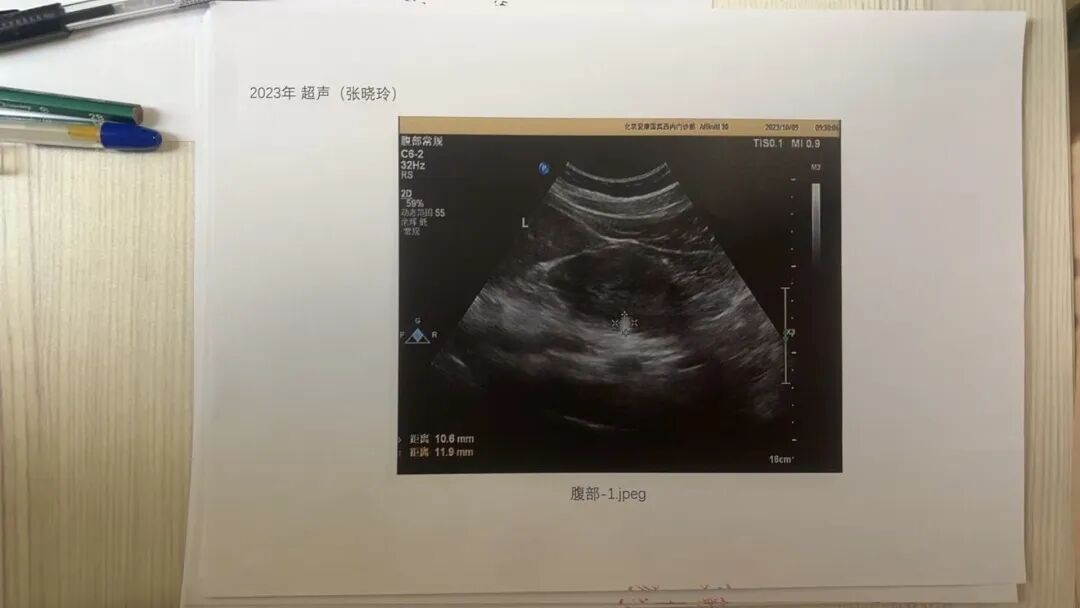

据张晓玲介绍,在北京市卫生健康委督促下,爱康国宾于12月8日提供了一份2021年至2023年的超声影像复印件。她表示,这些图片模糊不清,且没有姓名、没有ID、没有出生日期。“这是典型的‘三无图片’,无法识别身份。”

张晓玲称,爱康国宾提供的超声影像无姓名、ID等信息